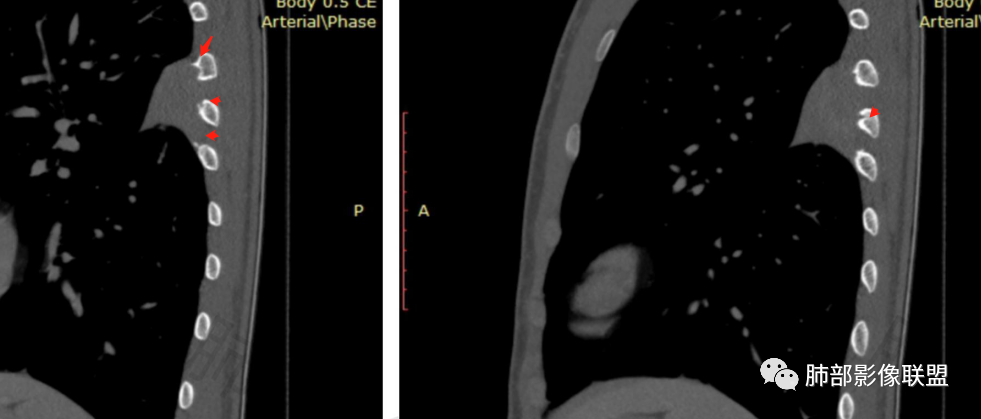

叶裂有变异,但病灶骑跨在叶裂上,外侧宽基底与胸壁相连,呈D子征

斜裂无偏移,病灶两侧膨隆,下缘背侧凹陷

病灶附近骨膜增厚、钙化

病灶明显突入胸壁,位于胸膜外

如果叶裂来源,附近胸膜应该朝外推移,不是朝内侧凸起

不是来自叶裂

肋骨改变明显,增生为主,提示慢性,偏良性,附近间隙显示欠佳,明显强化,倾向于胸壁来源神经源性肿瘤,其次胸膜SFT

2.左侧叶间裂后缘及胸壁区不规则块影,肺组织一侧边缘光整。密度不甚均匀,未见钙化,不均匀强化,未见明确支气管及肺血管影进入,也未能显示肋间动脉进入。

3.块影有沿胸膜生长蔓延趋势,可见胸膜尾征。胸壁侧边界不清,所经两处肋骨内侧缘骨皮质吸收破坏,局部硬化,边界可分辨。肋骨未见变形膨胀或葱皮样骨膜反应。注意没有胸水。